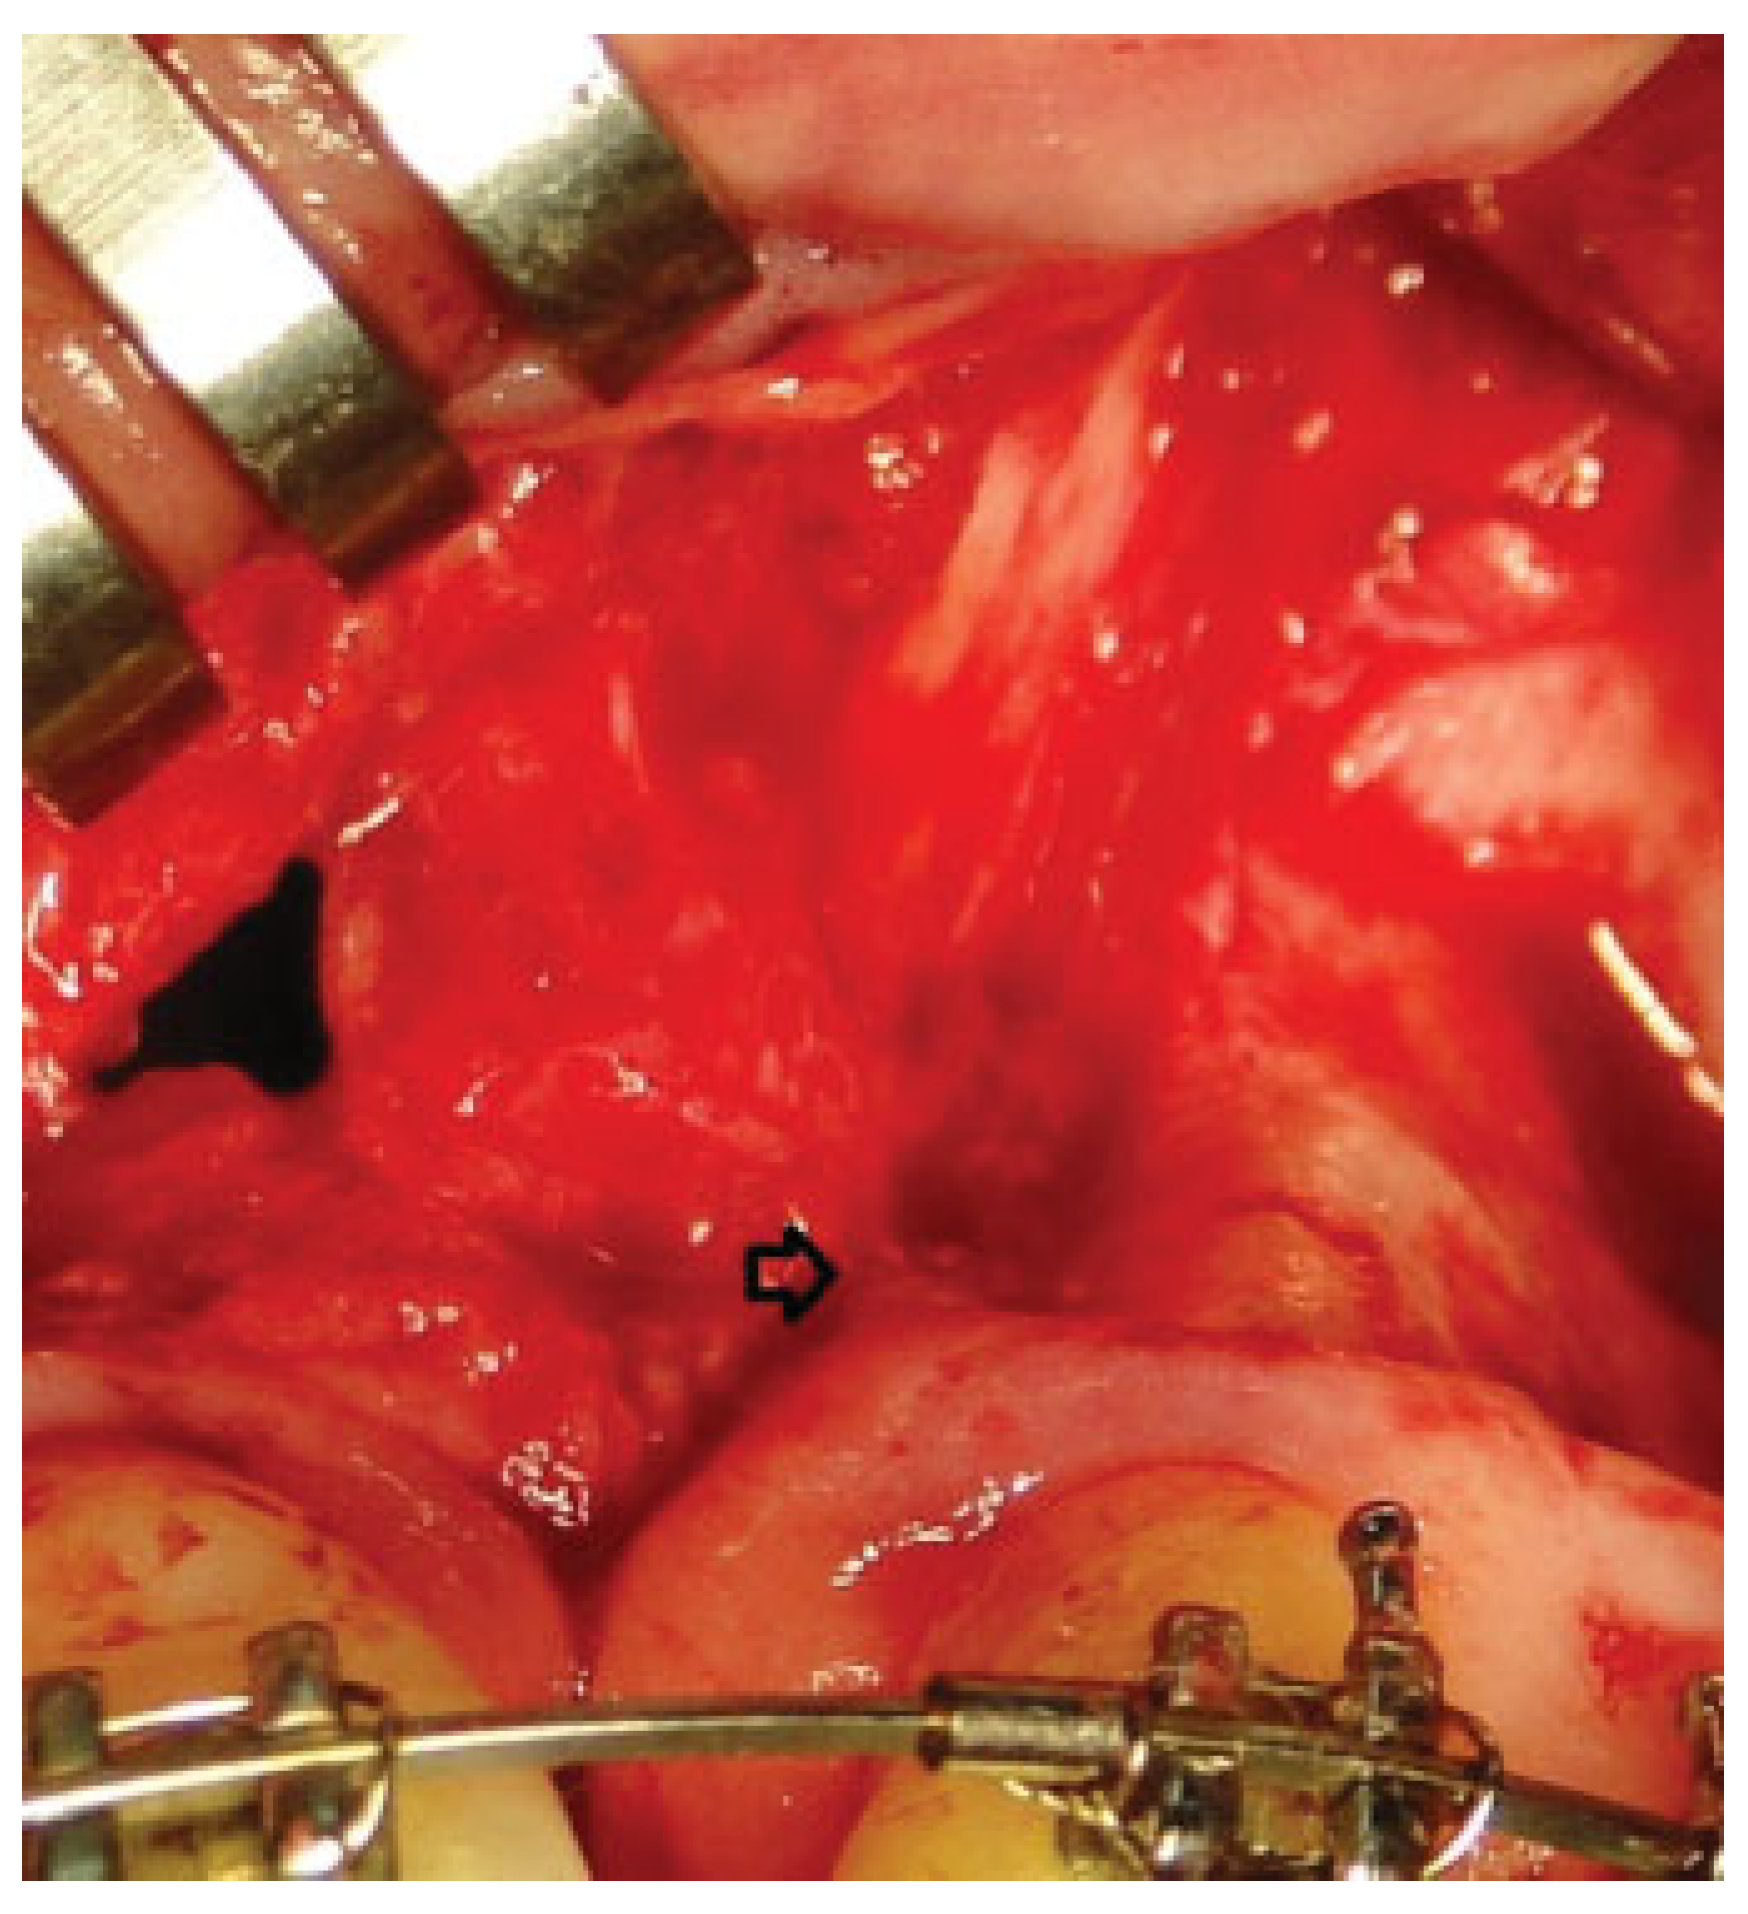

Alveolar bone grafting was performed under general endotracheal anesthesia. Incisions were made and gingival mucoperiosteal flaps were elevated in the standard fashion for alveolar bone grafting to create a suitable pocket (►Figure 1).

Figure 1.

Elevation of gingival mucoperiosteal flaps and dissection of the pocket.